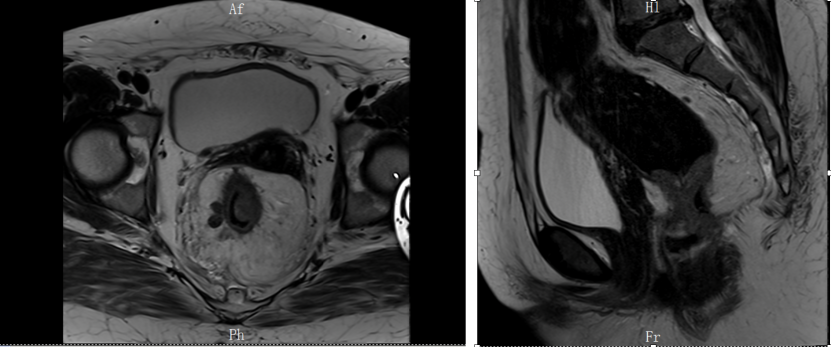

增强CT:可见直肠中上段肠壁增厚,考虑ca,盆腔多发淋巴结肿大,疑转移。

增强MRI:可见直肠肿物,侵及肠壁全层,肠壁外有多发肿大淋巴结。考虑直肠癌(T3N2Mx)。